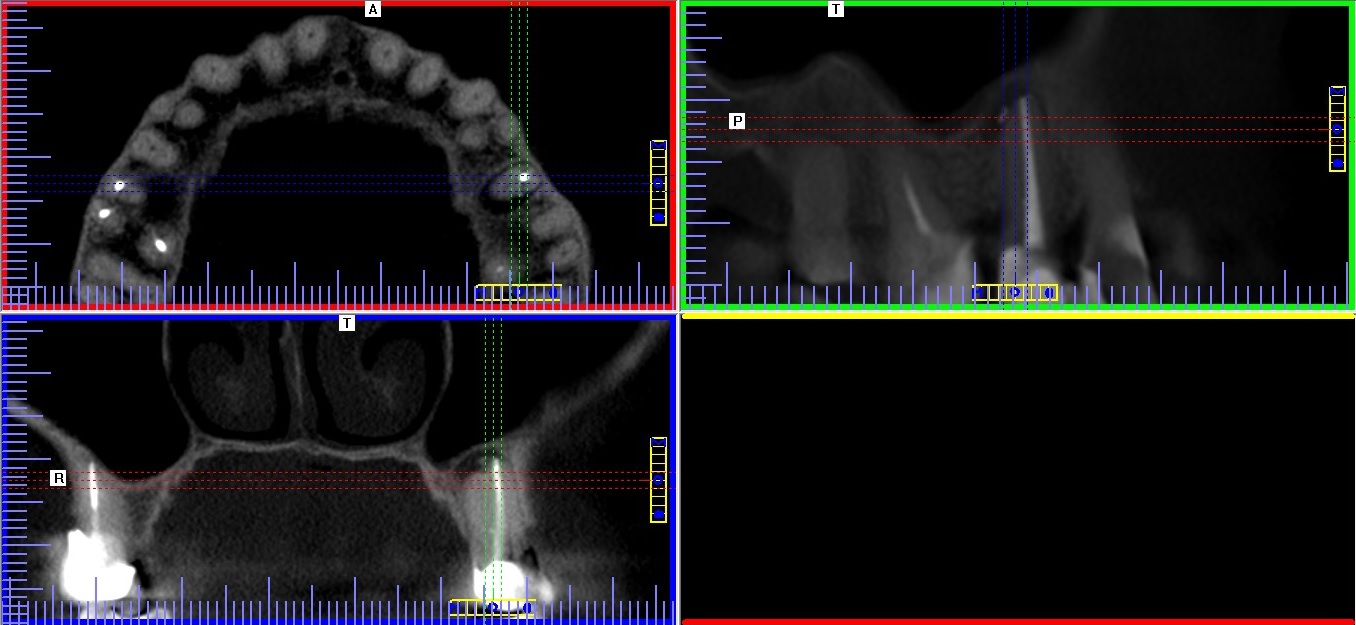

– Obrazowanie 3D, czyli tomografia – w endodoncji najczęściej wykorzystuje się tomografię komputerową wiązki stożkowej (cone bean computed tomography – CBCT) o tak zwanym małym polu obrazowania. Dzięki temu można uzyskać wyraźne, szczegółowe skany zęba przy stosunkowo małej dawce promieniowania i zachować zasadę ALARA (as low as reasonably achievable) dotyczącą ochrony radiologicznej. Według tej zasady dawka promieniowania musi być utrzymana na możliwie najniższym poziomie, w taki jednak sposób, aby nie ograniczać możliwości diagnostycznych w trakcie leczenia (6). Dzięki temu, że na skanach tomografii komputerowej uzyskujemy wirtualne przekroje w płaszczyźnie czołowej, strzałkowej i osiowej można dokładnie prześledzić budowę i ewentualne krzywizny kanału. Tomogramy pozwalają również wykryć kanały dodatkowe i znaleźć przyczyny ewentualnych niepowodzeń pierwotnego leczenia kanałowego (ryc. 5‑8). Gopikrishna i wsp. dzięki zastosowaniu tomografii komputerowej odkryli nietypową budowę zęba trzonowego górnego z dwoma kanałami podniebiennymi i tylko jednym kanałem policzkowym (7). W innej publikacji opisano przypadek pierwszego zęba trzonowego szczęki z pięcioma kanałami, w tym dwoma kanałami podniebiennymi (8). W badaniu Huumonen i wsp. dzięki wykorzystaniu tomografii stwierdzono obecność kanału dodatkowego (MB2) w 30 z 39 ocenianych zębów trzonowych szczęki. Jednocześnie zaobserwowano, że aż 27 kanałów dodatkowych nie zostało wykrytych, co spowodowało powstanie zmian zapalnych w tkankach okołowierzchołkowych w przypadku 22 z 27 nieleczonych kanałów (9).

Ryc. 5. Tomogram szczęki. Widoczny poprzeczny, „wirtualny” przekrój przez korzeń zęba 25 w około połowie jego długości: nieleczony kanał podniebienny, kanał policzkowy wypełniony.

Źródło: Olczak K. Wykorzystanie tomografii wolumetrycznej podczas ponownego leczenia kanałowego drugiego zęba przedtrzonowego szczęki. Mag Stomatol. 2019; 9: 23.

Ryc. 6. Tomogram szczęki. Widoczne „wirtualne” przekroje przez korzeń zęba 25 w trzech płaszczyznach, widoczne zmiany zapalne w tkankach okołowierzchołkowych i niewielka ilość uszczelniacza poza wierzchołkiem.